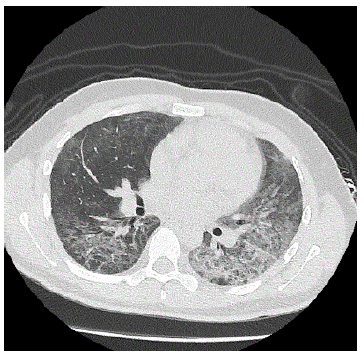

A las 48 horas de hospitalización se confirma diagnóstico de VIH, siendo derivado al hospital de referencia para continuar estudio y tratamiento. En dicho centro se realiza tomografía axial computarizada que confirma patrón de neumonía tipo Pneumocistis jirovecci, tal como se evidencia en las Figuras 2 y 3. Por normativa local, el inicio de la triterapia se indica en el hospital de referencia.

Tomografía axial computarizada de corte transversal de tórax que evidencia patrón de vidrio esmerilado y broncograma aéreo hacia las bases.

Figura 2: Tomografía axial computarizada de corte transversal de tórax que evidencia patrón de vidrio esmerilado y broncograma aéreo hacia las bases.

Fuente: Documento obtenido durante la realización del estudio.